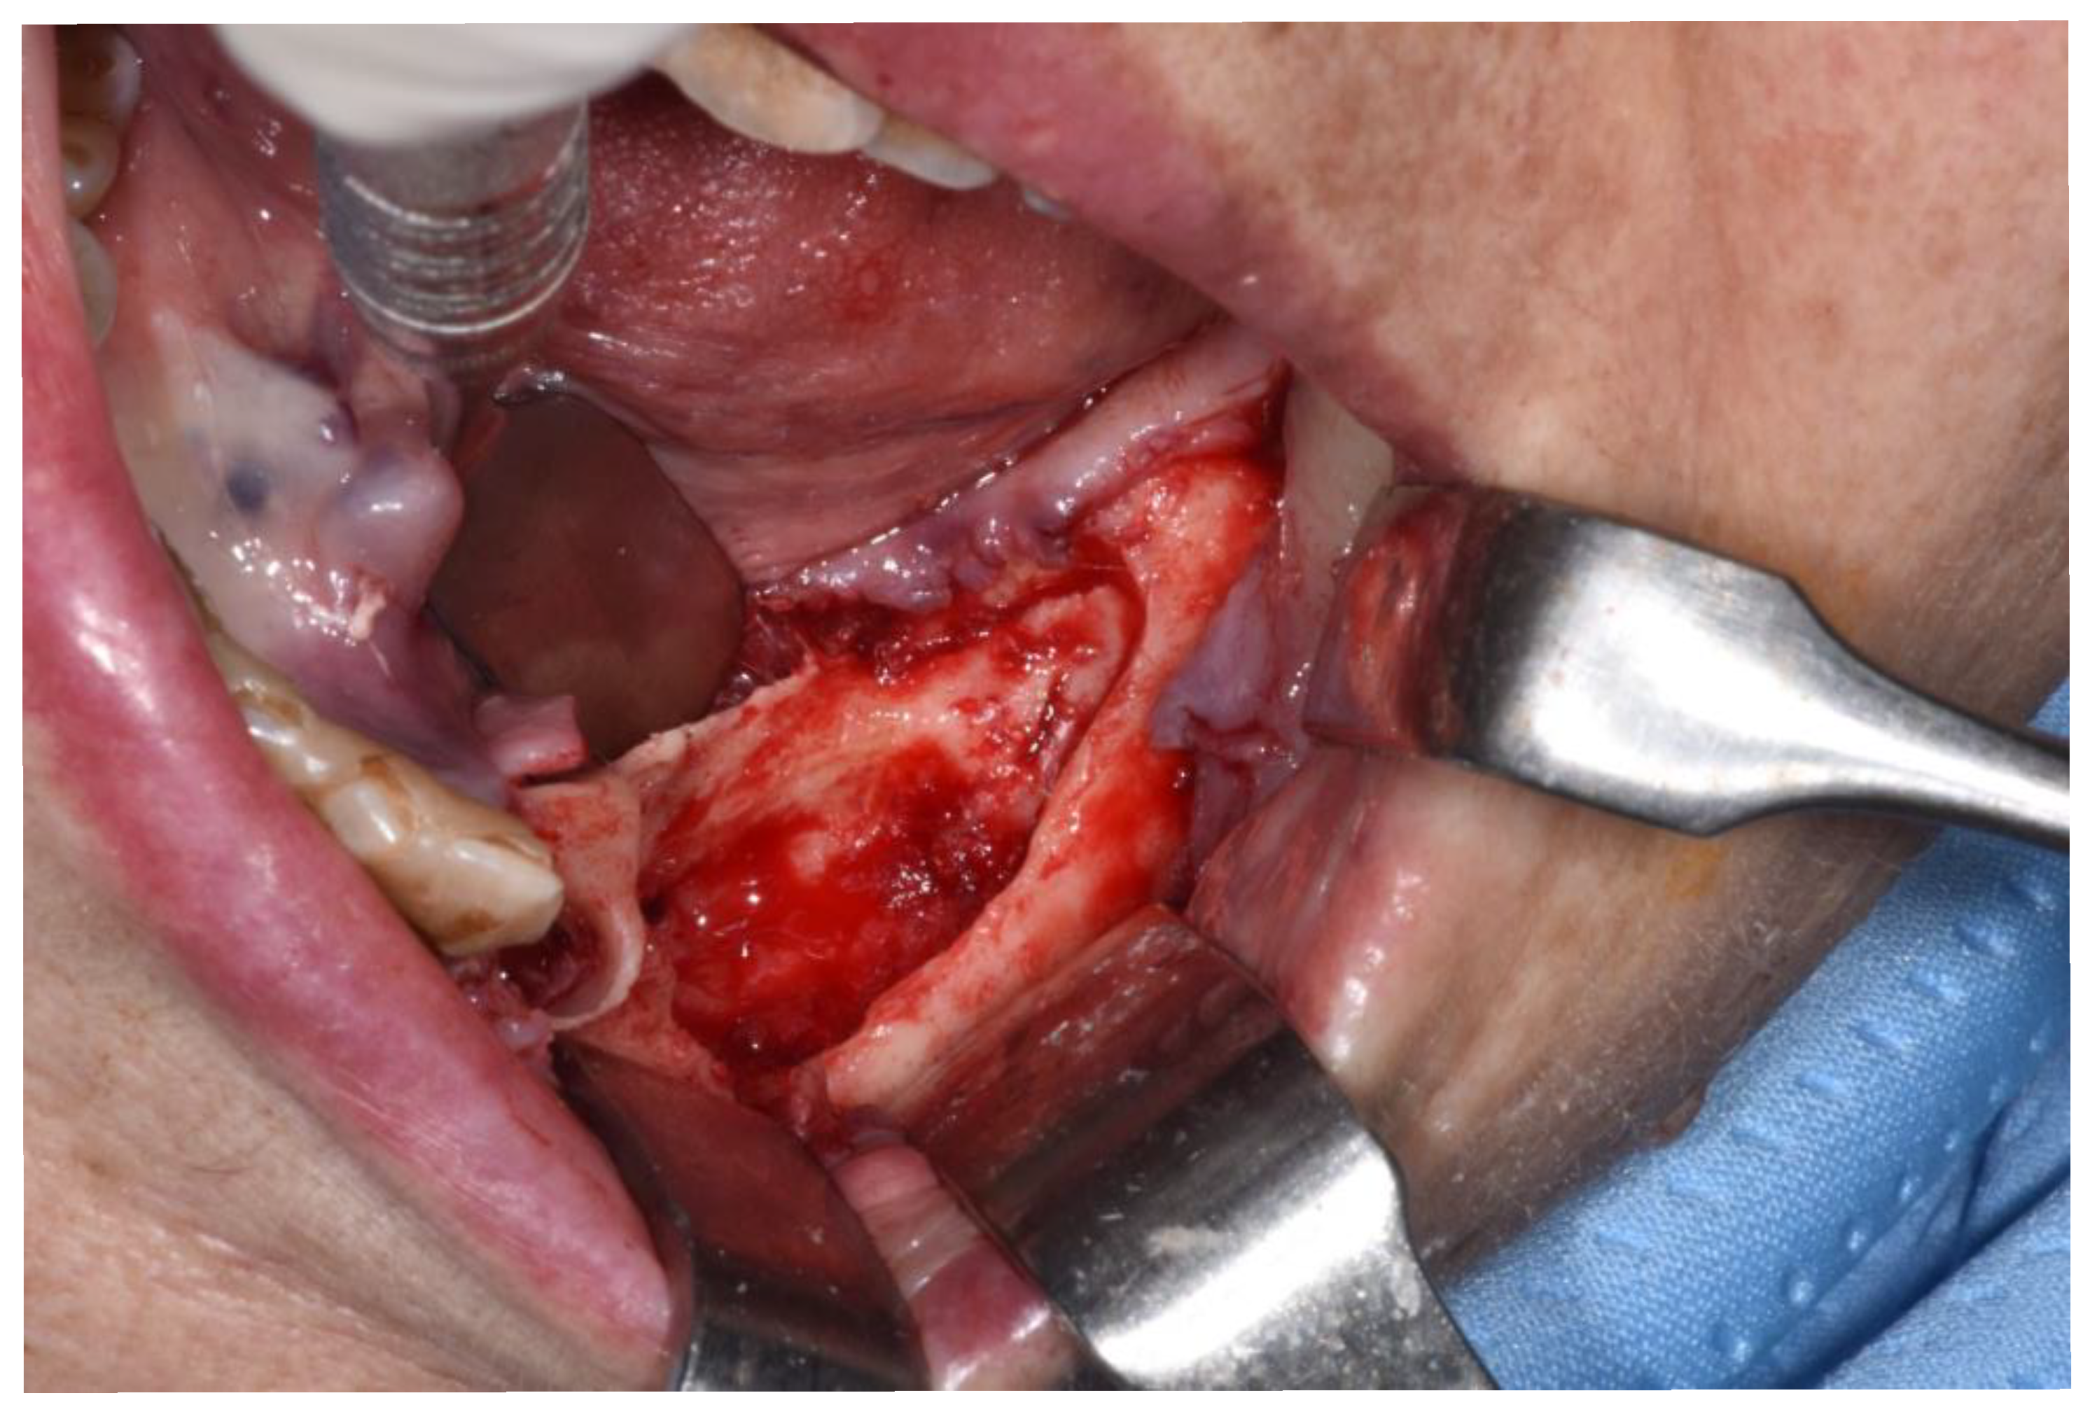

Figure 6.

Revision of the cavity until observing bleeding bone.

Patients are referred to the Osteonecrosis of the Jaw Treatment Center, School of Dentistry, University of Messina mostly by their oncologist. On arriving at the center, patients are diagnosed with MRONJ based on the clinical and radiological findings in order to distinguish focal and diffused forms. Routine procedures at first examination include oral swab and pharmacological treatment prescription with systemic antibiotics. Initial treatment is amoxicillin plus clavulanic acid in combination with metronidazole at 250 mg; subsequently, patients are switched to targeted antibiotic therapy on the basis of the antibiogram result. Eight to ten weeks after the initiation of pharmacological treatment, unchanged and progressive forms urdergo surgical treatment [34]. The systematic application of this work flow ensures homogeneity in the patient sample in terms of antibiotic therapy (empiric vs. targeted therapy) and time to intervention (defined as time from MRONJ diagnosis to surgical procedure). The surgical approaches were defined according to literature [9,10,17,23,35,36] as previously described by our study group [25,26]. The surgery was performed in loco-regional anesthesia with intra-oral approach and consisted in the resection of the necrotic bone until reaching bleeding vital bone. Access to the osteonecrotic lesion was provided by a mucoperiosteal flap with total thickness sufficiently large to include the margins of the necrotic bone. The affected bone can be removed using ultrasonic bone surgery device. After removing the necrotic segment, if a sufficient quantity of soft tissue to obtain closure by first intention is present, the vestibular and the lingual mucoperiostal flaps were directly sutured on the defect without any release incision; otherwise, closure could be obtained using mucosal advancement flaps to allow for a tension-free suture. Figure 1, Figure 2, Figure 3, Figure 4, Figure 5 and Figure 6 show pre-surgical assessment and specimen harvesting during surgical procedure (Figure 1, Figure 2, Figure 3, Figure 4, Figure 5 and Figure 6).